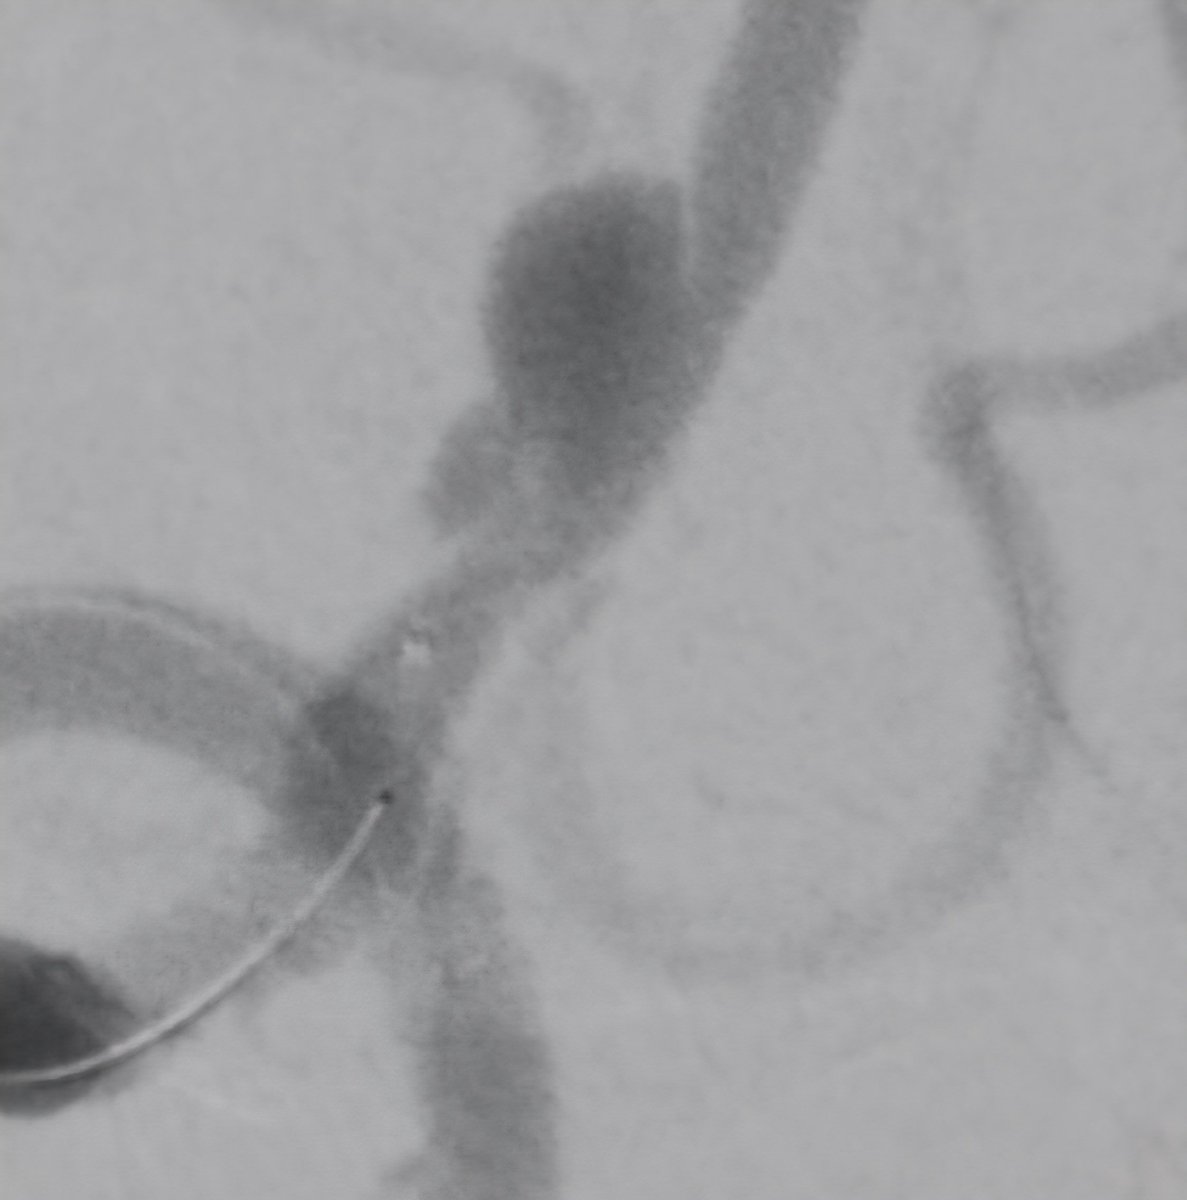

همه در یک بیمار. کاروتید راست:دایسکشن کاروتید چپ: تنگی شدید ورتبرال چپ: بسته شدن کامل از ابتدای شریان ورتبرال راست: دایسکشن و آنوریسم. درمان: استنت کویل در ورتبرال راست و نیز استنت کاروتید چپ. ادامه درمان با ضد پلاکت.